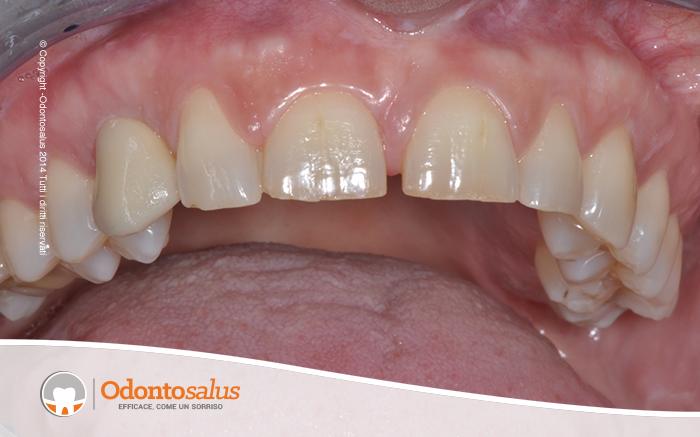

Il paziente si presenta in studio con il canino in inclusione (elemento 13).

Inizialmente è stato effettutao un trattamento ortodontico per riportare l’elemento incluso in arcata. Tuttavia, come a volte accade in relazione all’età del paziente, alla densità ossea o alla posizione del dente incluso, ortodonticamente non è stato possibile riallineare il canino con gli altri denti. Si è proceduto, pertanto, con l’incisione del lembo, la scopertura e l’estrazione del canino, il riempimento del deficit osseo creato, l’applicazione dell’impianto e, data la sua stabilità, l’inserimento del provvisorio nella stessa seduta.

A distanza di circa tre mesi è stato inserito l’elemento definitivo, per un ottimo risultato sia funzionale, salvaguardando la gengiva e l’osso, che estetico.